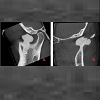

A 42-year-old female was referred to the Oral and Maxillofacial surgery clinic, complaining of a constant ‘contraction’ like movement of her jaw over a one-year period. She was also experiencing preauricular pain in the left temporo-mandibular joint (TMJ) region.She did not report any previous trauma.Clinical examination revealed no swelling or facial asymmetry therefore a full Orthopantomograph (OPG) radiograph was requested to assess for likely sources of the patient’s presenting complaints, which were expected to be a TMJ related disorder or dental pathology. However the radiograph revealed a radiopaque mass related to the left mandibular notch, which was not palpable clinically (Figure 1). A cone beam computed tomography (CBCT) scan reported an 18 x 13 x 14 mm bony mass arising from the left mandibular notch (Figure 2). The lesion had a pedunculated shape with a lobulated outline (Figure 3). The appearance of dense bone suggested an osteoma. Due to the radiographic appearance and peripheral nature of the lesion, the two main differential diagnoses established were a peripheral osteoma or an exostosis. Both lesions have similar histological appearances and therefore need to be differentiated clinically. Unlike the lesion in this case, exostoses are not usually solitary. In addition, lesions stop growing after puberty and are commonly related to areas of attached gingivae.By contrast, peripheral osteomas present as solitary, usually asymptomatic masses of long duration. Radiographically lesions are well circumscribed, oval and have a similar density to the surrounding bone. Histological investigation will be needed to confirm the type of osteoma present i.e. compact, cancellous, or mixed. However, peduncluated osteomas are usually cancellous in nature [5].